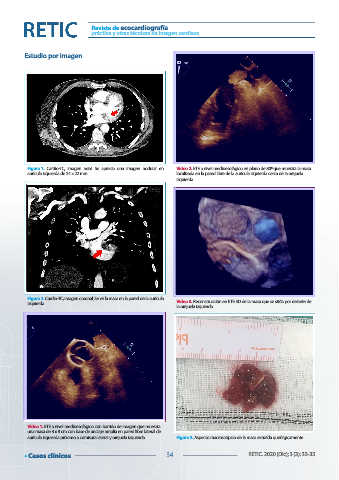

Figura 1. Cardio-TC, imagen axial. Se aprecia una imagen nodular en Vídeo 2. ETE a nivel medioesofágico en plano de 80º que muestra la masa

aurícula izquierda de 24 x 22 mm localizada en la pared libre de la aurícula izquierda cerca de la orejuela

izquierda

Figura 2. Cardio-TC, imagen coronal. Se ve la masa en la pared de la aurícula Vídeo 3. Reconstrucción en ETE 3D de la masa que se sitúa por delante de

la orejuela izquierda

Vídeo 1. ETE a nivel medioesofágico con barrido de imagen que muestra

una masa de 3 x 3 cm con base de anclaje amplia en pared libre lateral de

aurícula izquierda próximo a comisura lateral y orejuela izquierda Figura 3. Aspecto macroscópico de la masa extraída quirúrgicamente